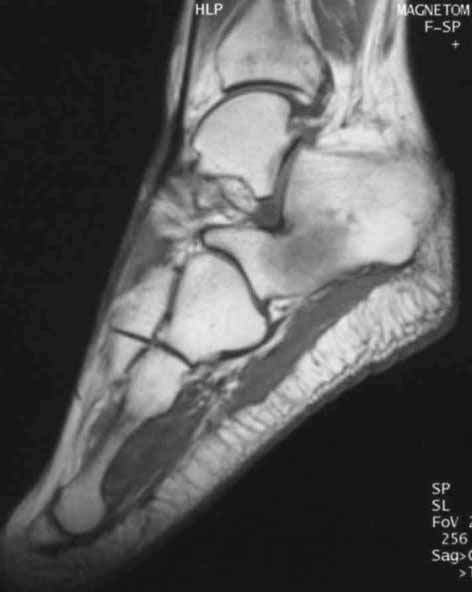

CaseTH01

あなたの診断はWhat is your first impression?